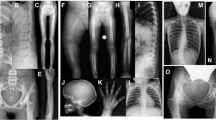

Camurati-Engelmann disease (CED, MIM 131300) is an autosomal dominant, progressive diaphyseal dysplasia characterized by hyperosteosis and sclerosis of the diaphyses of long bones1. We recently assigned the CED locus to an interval between D19S422 and D19S606 at chromosome 19q13.1–q13.3 (ref. 2), which two other groups confirmed3,4. As the human transforming growth factor-β1 gene (TGFB1) is located within this interval5, we considered it a candidate gene for CED.